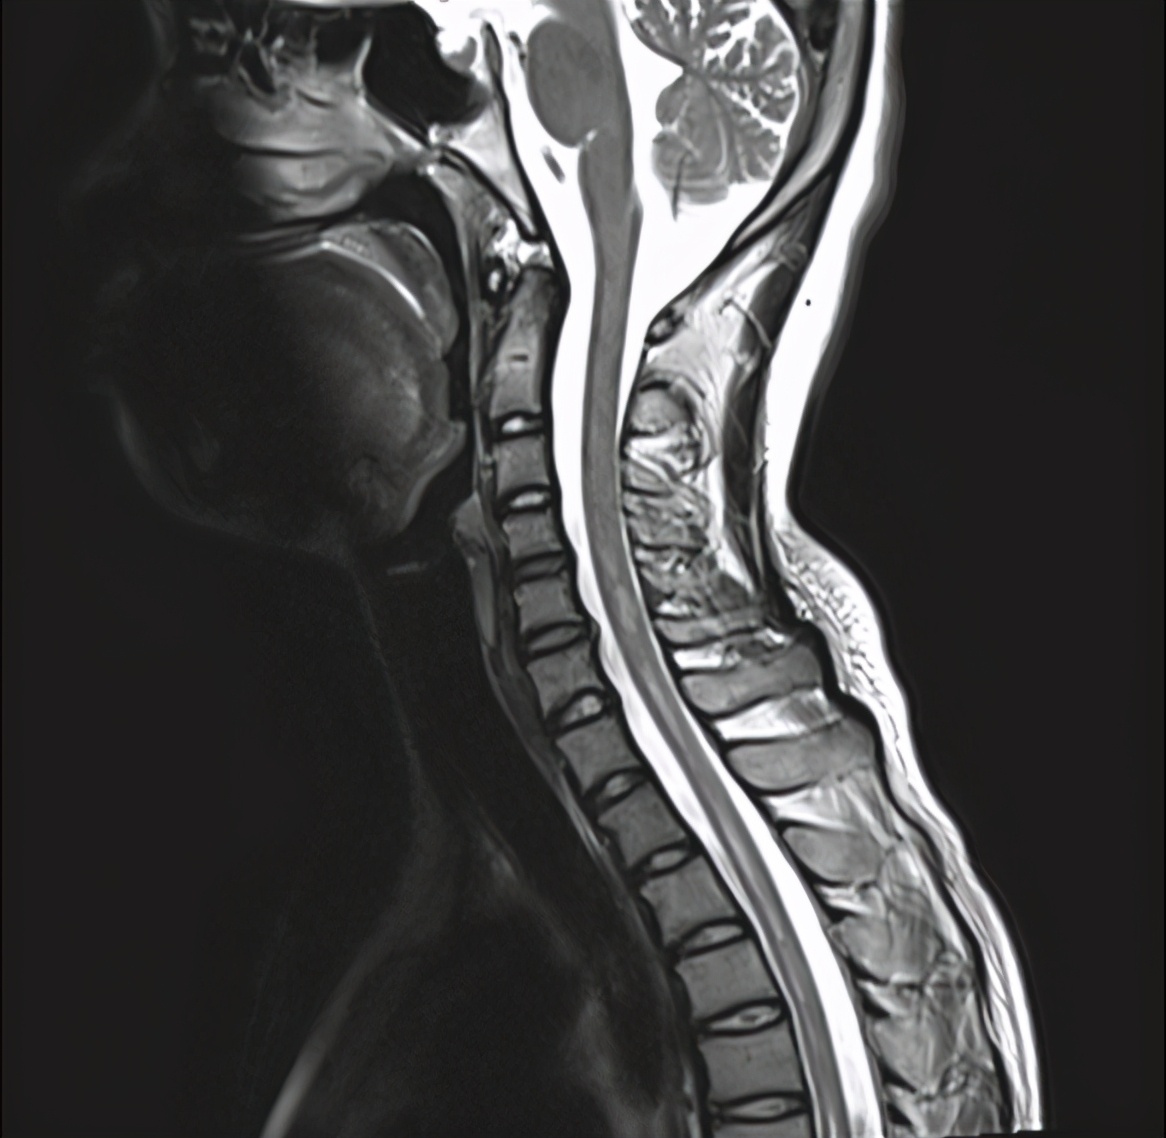

此时脊髓MRI结果:

图:颈胸椎多发长段异常信号影

综合患者脑脊液及脊髓MRI结果,再联系患者病史,结核合并视神经脊髓谱系病NMOSD诊断明确。我们再次请药学部、眼科及神内科会诊后,建议给予500mg的甲基强的松龙静脉冲击治疗,联合丙种球蛋白10g连续5天;第6天甲强龙减量240mg / d,第9天减量120mg / d,第10天改为35mg(1mg/kg)口服强的松继续治疗。激素治疗同时口服异烟肼300mg、利福平450mg、吡嗪酰胺750mg。